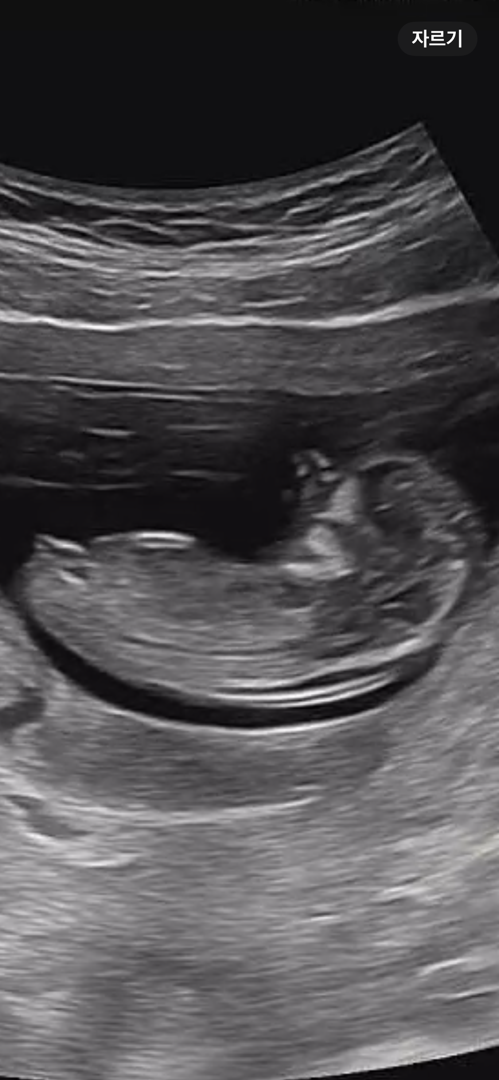

11주 4일 각도법 봐주세용🫡

니프티를 했지만 긴 연휴때문에 늦게 결과가 나온대요ㅠㅠ 도와주세요 플리ㅣ즈~~💕